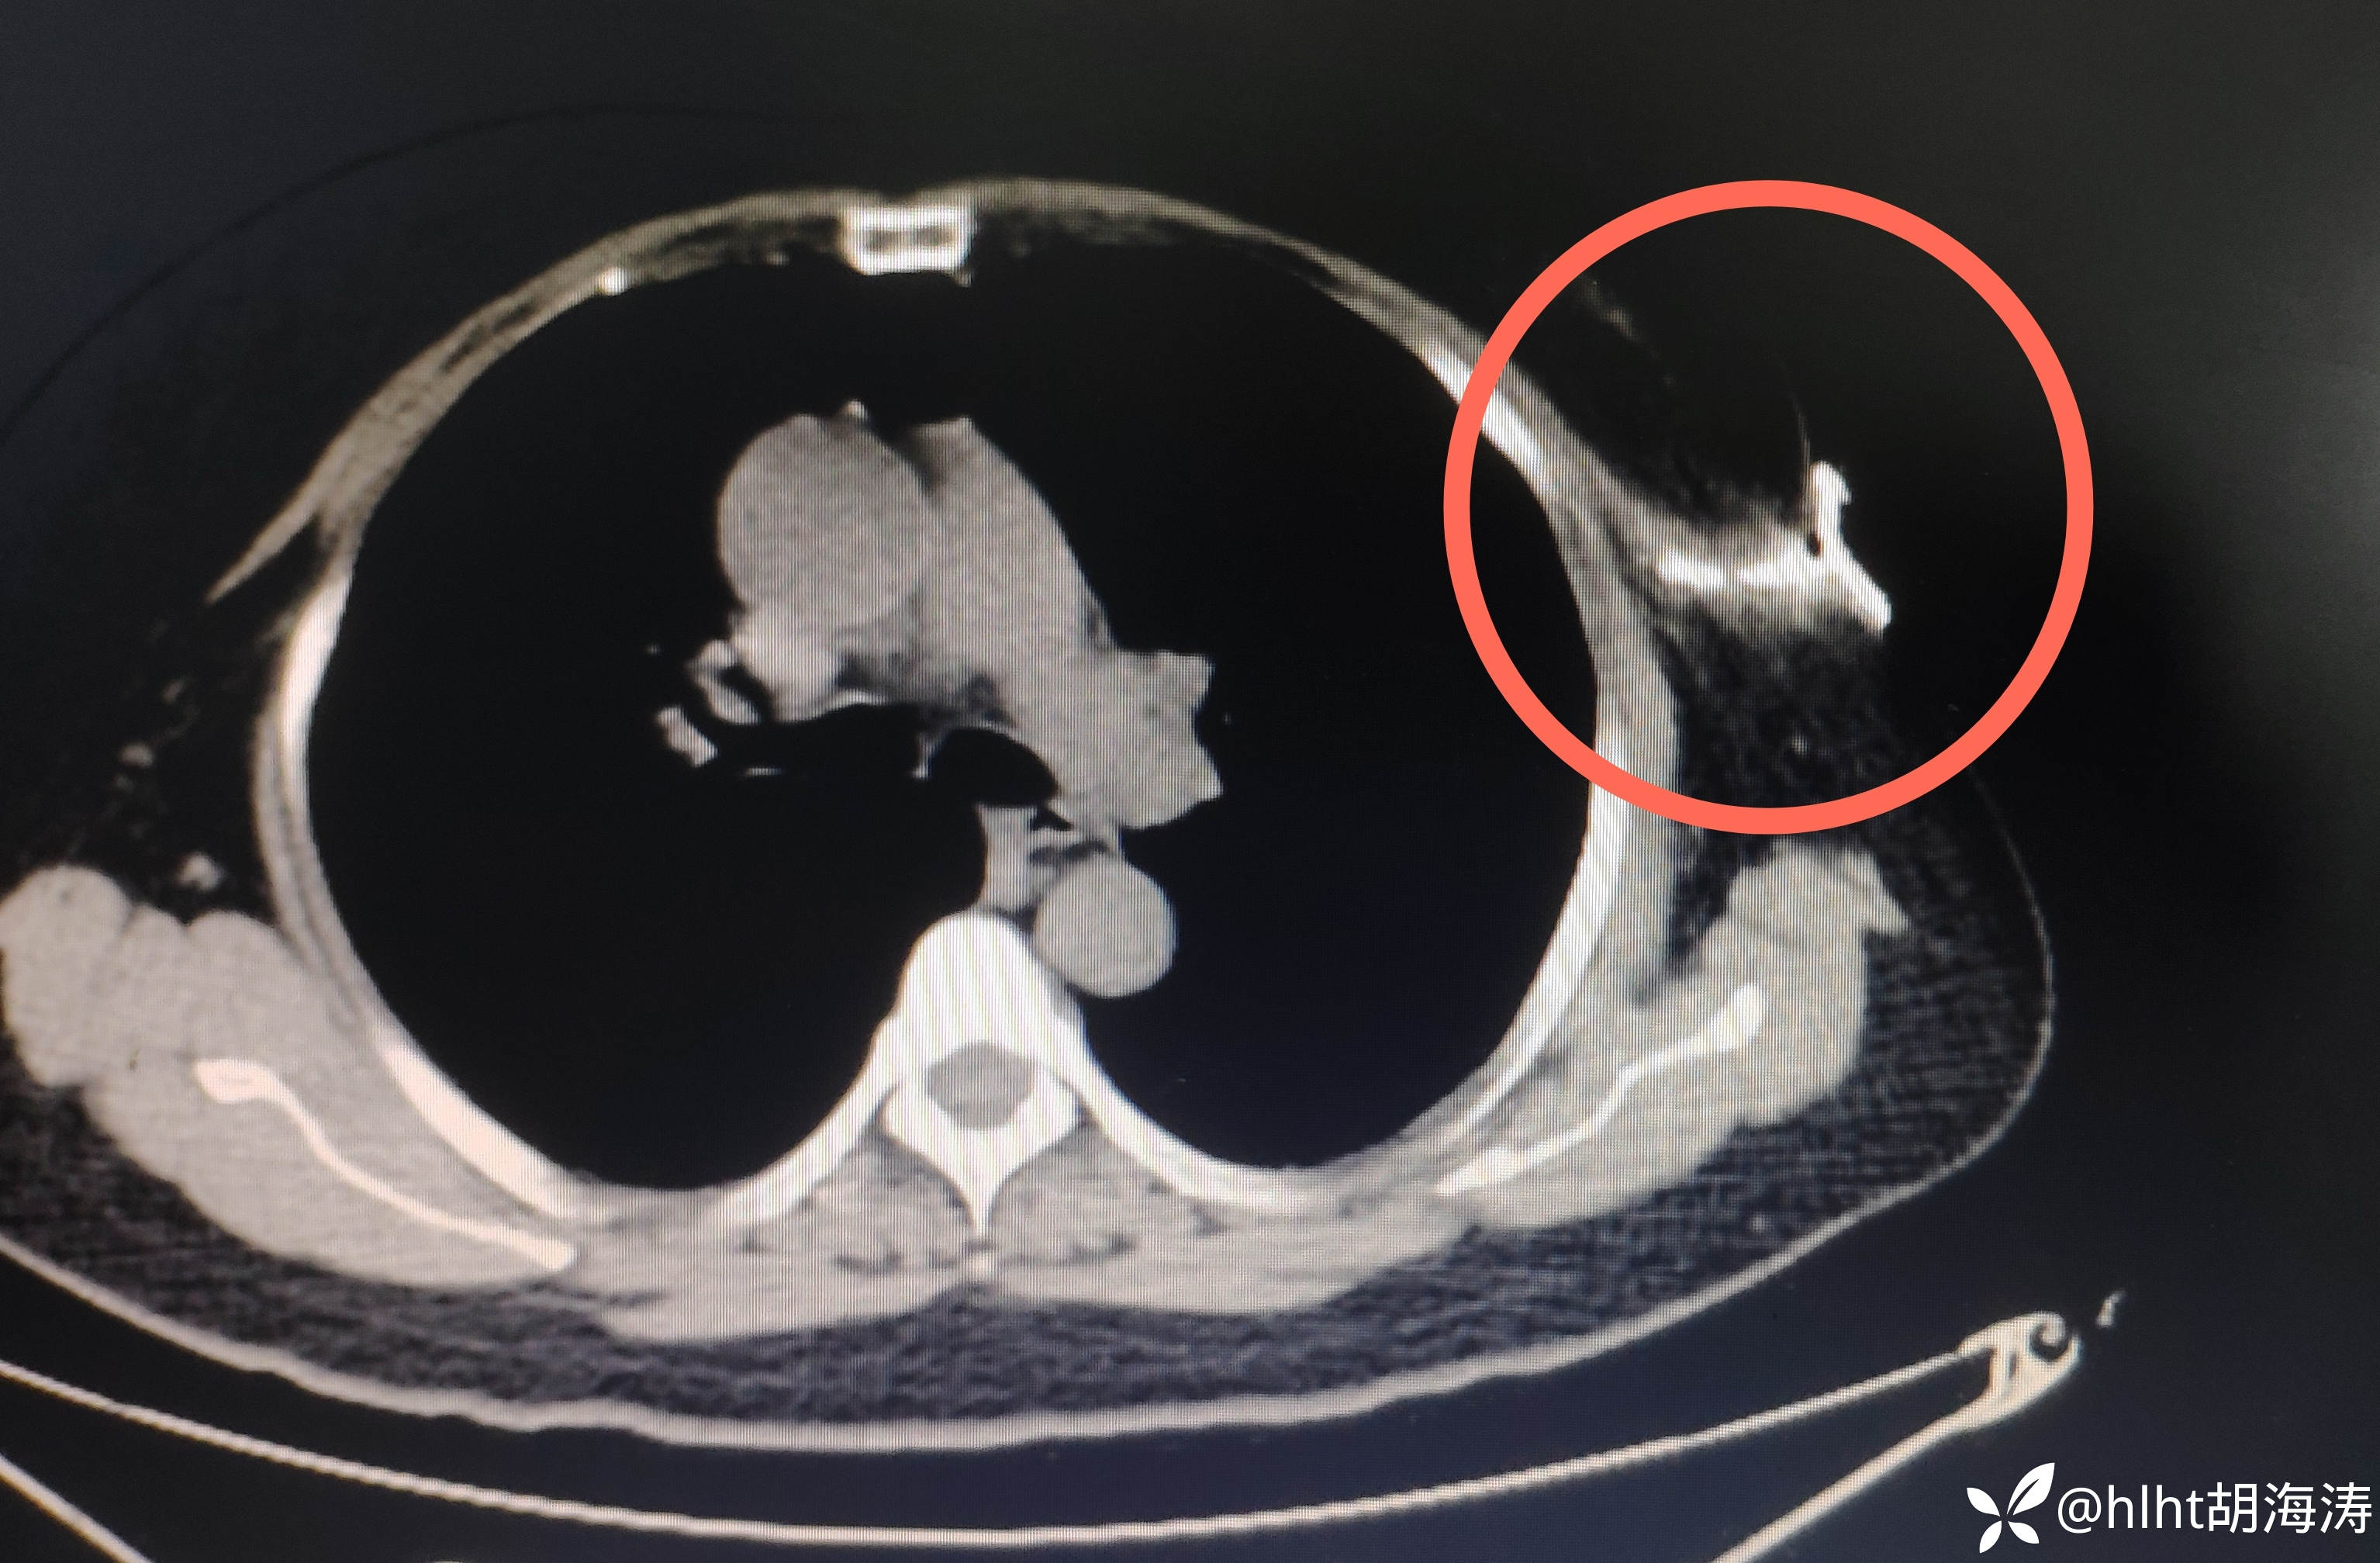

CT平扫